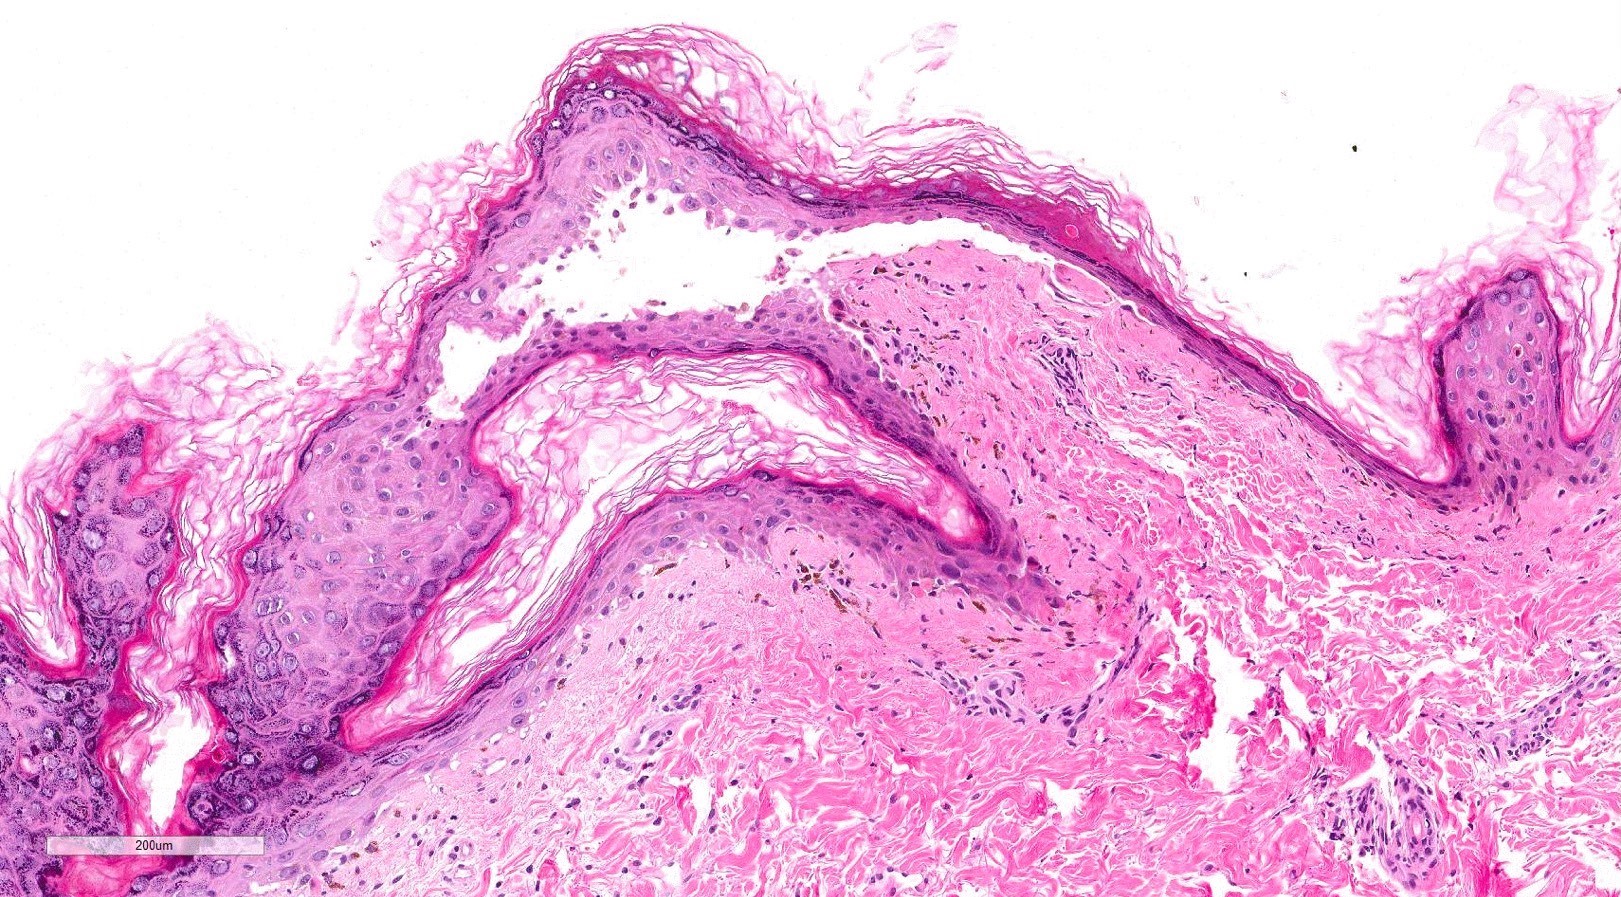

- Chronic GVHD (Biol Blood Marrow Transplant 2015;21:589, Patterson: Weedon's Skin Pathology, 4th Edition, 2015)

- Chronic lichenoid GVHD

- Acanthosis, orthohyperkeratosis, parakeratosis with hypergranulosis

- Underlying band-like lymphocytic infiltrate with basal layer vacuolization and apoptotic keratinocytes

- Periadnexal inflammation can be present

- May be difficult to distinguish from lichen planus without clinicopathologic correlation; satellite cell necrosis is the most helpful clue in GVHD biopsies to distinguish it from lichen planus

- Chronic sclerodermoid GVHD

- Dermal sclerosis (thickened compact collagen with loss of periadnexal fat)

- Manifests with localized morphea-like features, diffuse sclerosis or lichen sclerosus-like features

- Localized morphea-like features and diffuse sclerosis are largely confined to the reticular dermis or subcutaneous septa with little or no epidermal involvement

- Lichen sclerosus-like GVHD: collagen alteration is confined to the papillary dermis (hyalinzation of the papillary dermis), often with residual interface changes characterized by the presence of mild vacuolar alteration, melanophages and sparse superficial perivascular lymphocytic infiltrate

- Chronic lichenoid GVHD

Microscopic (histologic) images

Contributed by Silvija P. Gottesman, M.D. and Ohoud Aljarbou, M.D.